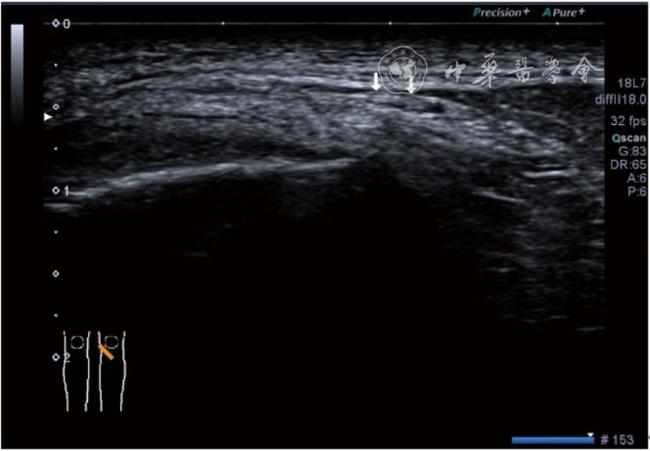

4.神经卡压液压松解加药物注射治疗。膝关节神经卡压主要涉及膝内上支、膝外上支、膝内下支、髌下支。可根据神经支配区域的临床检查确定卡压神经。临床上隐神经髌下支卡压常见。隐神经髌下支从隐神经发出后穿缝匠肌至膝内前下方,与深筋膜紧密相连(图24)。隐神经髌下支卡压出现膝关节内下侧酸痛、麻木,胫骨内侧髁压痛阳性,Tinel征阳性,局部皮肤痛觉减退。确定诊断后可行隐神经髌下支液压松解。患者平卧位,膝关节屈曲30°,下面垫一软枕。一般选用10 MHz以上超声探头,穿刺区域常规消毒,探头涂抹耦合剂后套入无菌手套碘伏消毒或使用无菌耦合剂。首先扫查神经短轴切面,确定神经后旋转为长轴切面引导注射。选用25G穿刺针头,抽吸0.5%利多卡因4 ml+地塞米松3 mg,从近端穿刺,沿神经表面纵轴方向,确定针尖在神经膜外后推注药物进行松解,注射完毕后拔出针头(图25),局部压迫2分钟,创可贴覆盖。

图24 隐神经髌下支卡压超声图像